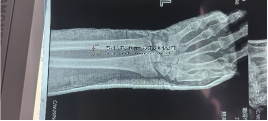

ORTHOFIX 外固定支架的優(yōu)勢: 1.單邊固定,輕便,固定可靠 2.手術(shù)時(shí)間短,操作簡單 3.微創(chuàng)手術(shù),不影響骨折端血供 4.無須二次手術(shù),門診即可拆除 5.支架與骨干長軸一致···

術(shù)前影像術(shù)前影像術(shù)中透視術(shù)中透視術(shù)中透視術(shù)中透視安裝外架術(shù)后外觀及影像術(shù)后外觀及影像術(shù)后外觀及影像本文轉(zhuǎn)載自好大夫平臺:···